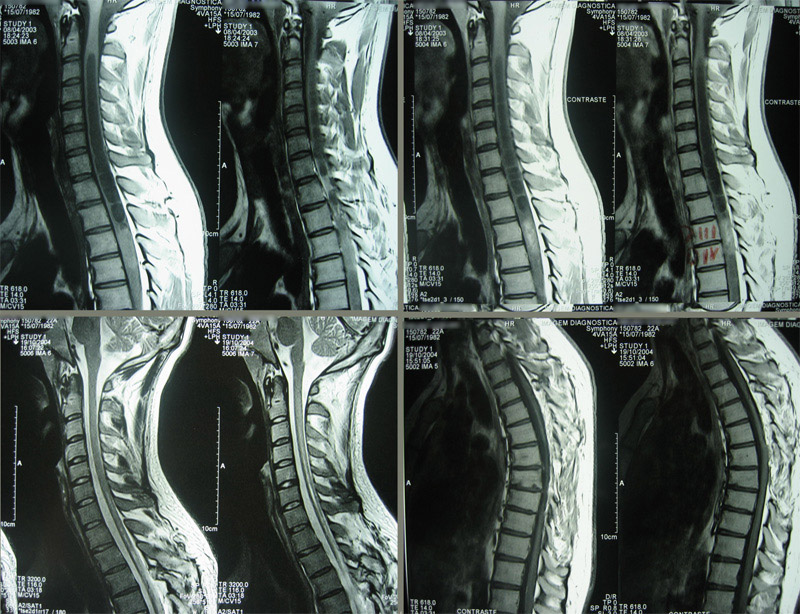

Pré e pós operatório de tumor intramedular cervical.